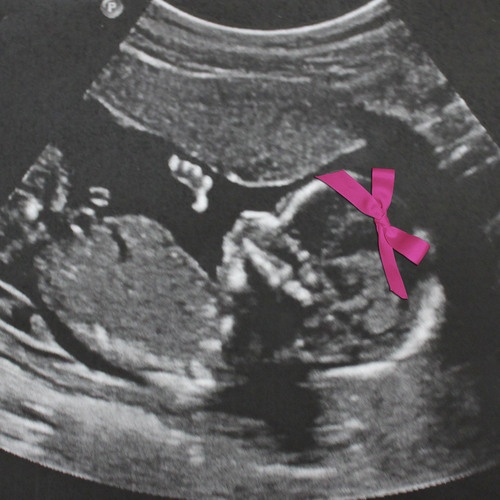

Our little baby girl!

Here she is shying away from the camera! A shy girl for now…